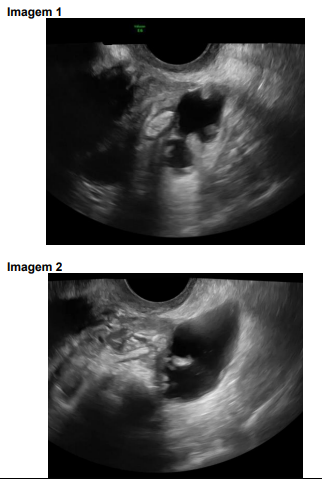

Nas imagens 1 e 2 estão representados dois sinais ecográficos de hidrossalpinge.

As imagens ecográficas representam, respectivamente: